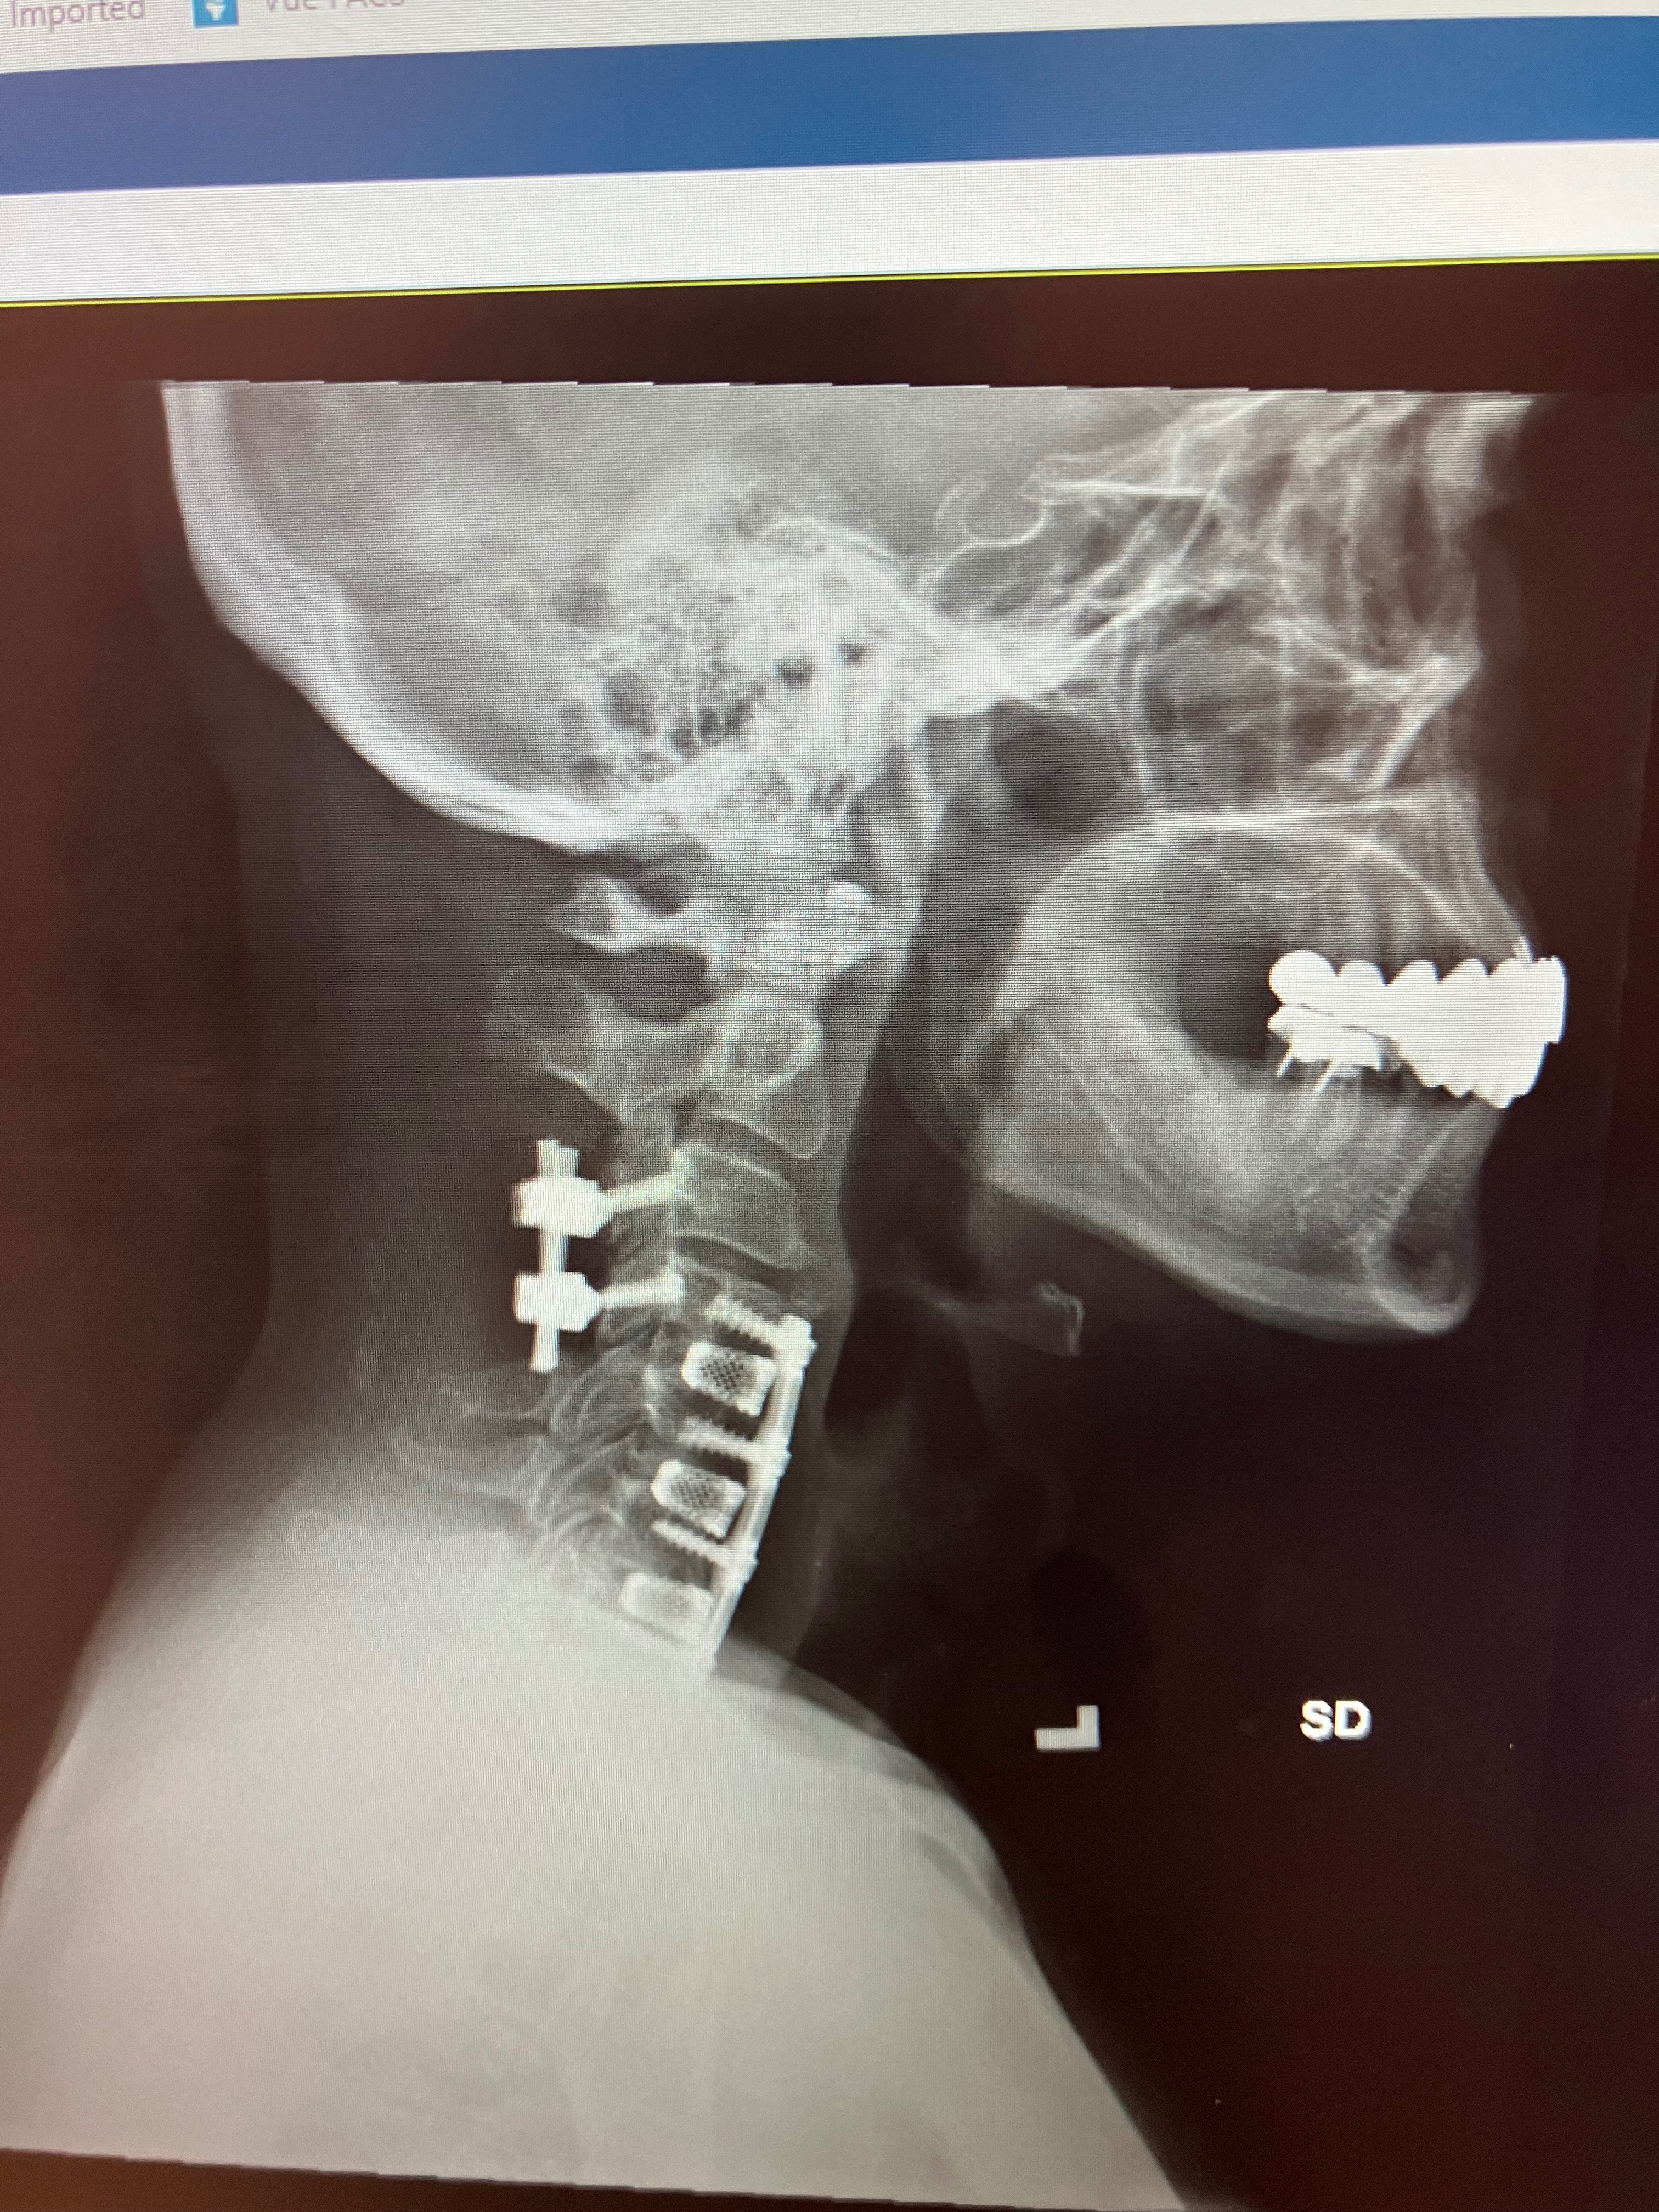

After a 7-hour emergency surgery, I was told I might never walk again. But I was determined to prove otherwise. With intense therapy and support from my family—especially my daughter, who’s studying nursing—I managed to take my first steps again with the help of special equipment.

While I’ve made progress, I’m still facing total body numbness and serious nerve damage. I suffer daily from constant burning, tingling, and electric-like pain caused by a 9mm bump on my spinal cord blocking all the signals to reach my brain. Doctors say the only real solution is advanced spinal cord surgery and stem cell treatment not covered by insurance.

I’m asking for your help to raise money for life-changing surgery and regenerative treatments led by one of the top neurosurgeons in the country, Dr. Kevin Foley in Memphis, TN. He’s had success treating injuries just like mine, including professional NFL athlete once told they’d never walk again.